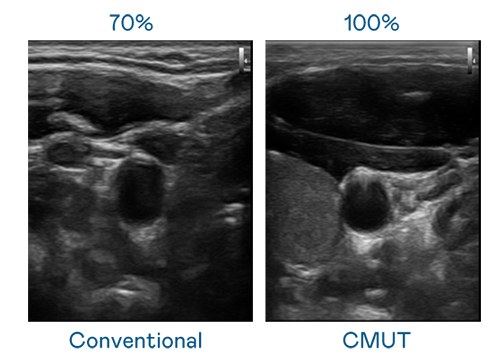

CMUT 技术是一种用电容式微机电元件来产生超音波讯号的技术。与传统 PZT 压电式技术相比,CMUT 频宽增加 30%,更宽频的超音波讯号让影像解析度大幅提升,是实现高影像品质医疗超音波扫描、促进精准医疗发展的关键技术。

大频宽带来超清晰影像

超音波影像的解析度高低,首先取决于探头能发出的讯号频宽。k1体育 CMUT 可提供高清晰的超音波讯号,提供高频宽、高灵敏度、影像纹理细节更高的超音波影像,协助医护人员缩短影像判读时间及利用精准的医疗影像进行诊断。